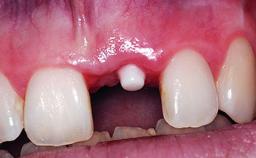

A 49-year-old female patient was referred for implant therapy to replace the upper right central incisor (tooth 11). The tooth had been assessed by an endodontist who diagnosed a vertical fracture of the root. The tooth had a hopeless prognosis and needed to be extracted. The patient was healthy and was not taking any medications. She was allergic to penicillin. The patient had high esthetic demands but her expectations were realistic. The extraoral examination revealed no facial asymmetries. The right temporomandibular joint demonstrated an opening click but was otherwise asymptomatic. The lip line was high with a significant gingival display.